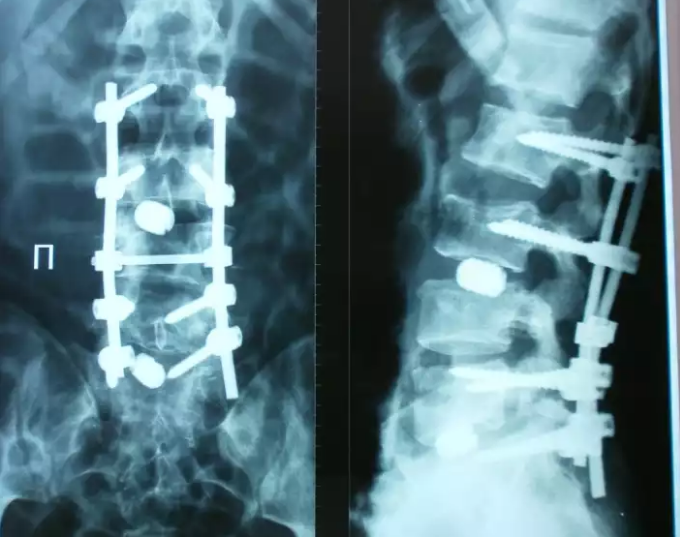

Медицинские снимки: рентген позвоночника сбоку